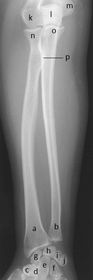

a. radius b. ulna c. trapezium d. trapezoid e. capitate f. hamate g. scaphoid h. lunate i. triquetrium j. pisiform k. capitulum l. olecranon process m. medial epicondyle n. radial head o. coronoid tubercle p. radial tuberosity